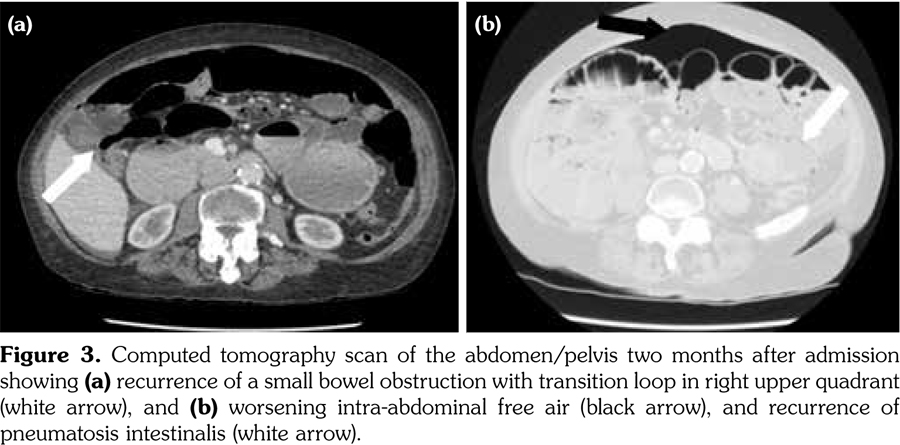

Two months following admission, a routine CT scan revealed recurrence of intra-abdominal free air (Figure 3). However, given her stable symptomatology, it was decided that she did not require re-admission. Treatment of SIBO, which was deemed to have been the cause of her benign PI, was continued with oral antibiotics and since then she has had complete resolution of her abdominal pain and diarrhea.